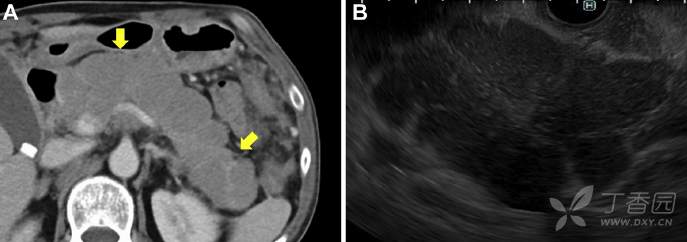

辅助检查:WBC1700/mL (正常值 3300–8600/mL), CD4细胞计数 86/mL, LDH 838 U/L (正常值124–222U/L),淀粉酶123 U/L (16–52 U/L),血清可溶性白介素2受体(sIL-2R) 2739 U/mL (正常值121–613 U/mL)。腹部增强CT所见如图A,EUS所见如图B。

请问:诊断是什么?

A 急性胰腺炎 B 自身免疫性胰腺炎 C 药物性胰腺炎 D 胰腺淋巴瘤 E 胰腺多发囊肿